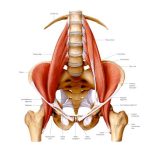

– Thận nằm sau phúc mạc, được bao quanh bởi Gerota fascia

– Mạc cơ tương liên: Fascia của Cơ thắt lưng – chậu (Psoas – Iliacus)

– Thoracolumbar fascia (mạc ngực – thắt lưng): nối Thận – Cột sống – Cơ dựng sống – Cơ chéo bụng)

2- Liên kết cơ – xương – khớp: Cơ liên quan trực tiếp:

– Cơ Psoas Major, Quadratus Lumborum, cơ dựng sống

(Hình ảnh đính kèm: )